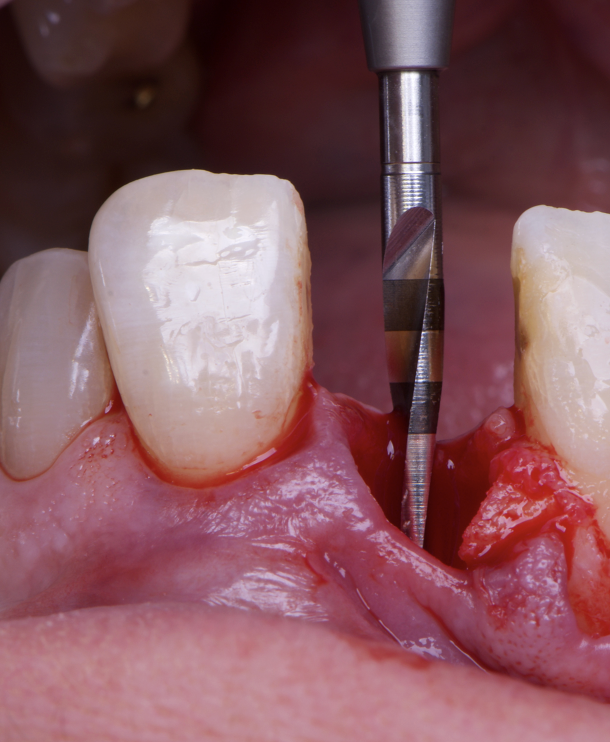

The surgical protocol began with the atraumatic extraction of tooth 1.1 to preserve as much of the alveolar socket as possible. Immediately following extraction, an N1 implant was placed into the socket using a guided surgical approach to ensure ideal three-dimensional positioning. The “one abutment one time” technique was applied to minimize soft tissue manipulation during the healing phase, which is particularly important in esthetic areas.

Given the significant buccal defect, guided bone regeneration (GBR) was performed simultaneously. A mixture of autologous bone and creos™ xenogain™ was applied to the defect and covered with a resorbable creos™ membrane to restore ridge width and support the buccal contour. In addition, a connective tissue graft was harvested and placed in the vestibular region to increase the thickness of keratinized mucosa. This combined approach addressed both hard and soft tissue deficiencies, providing the biological foundation for a stable and esthetic outcome.